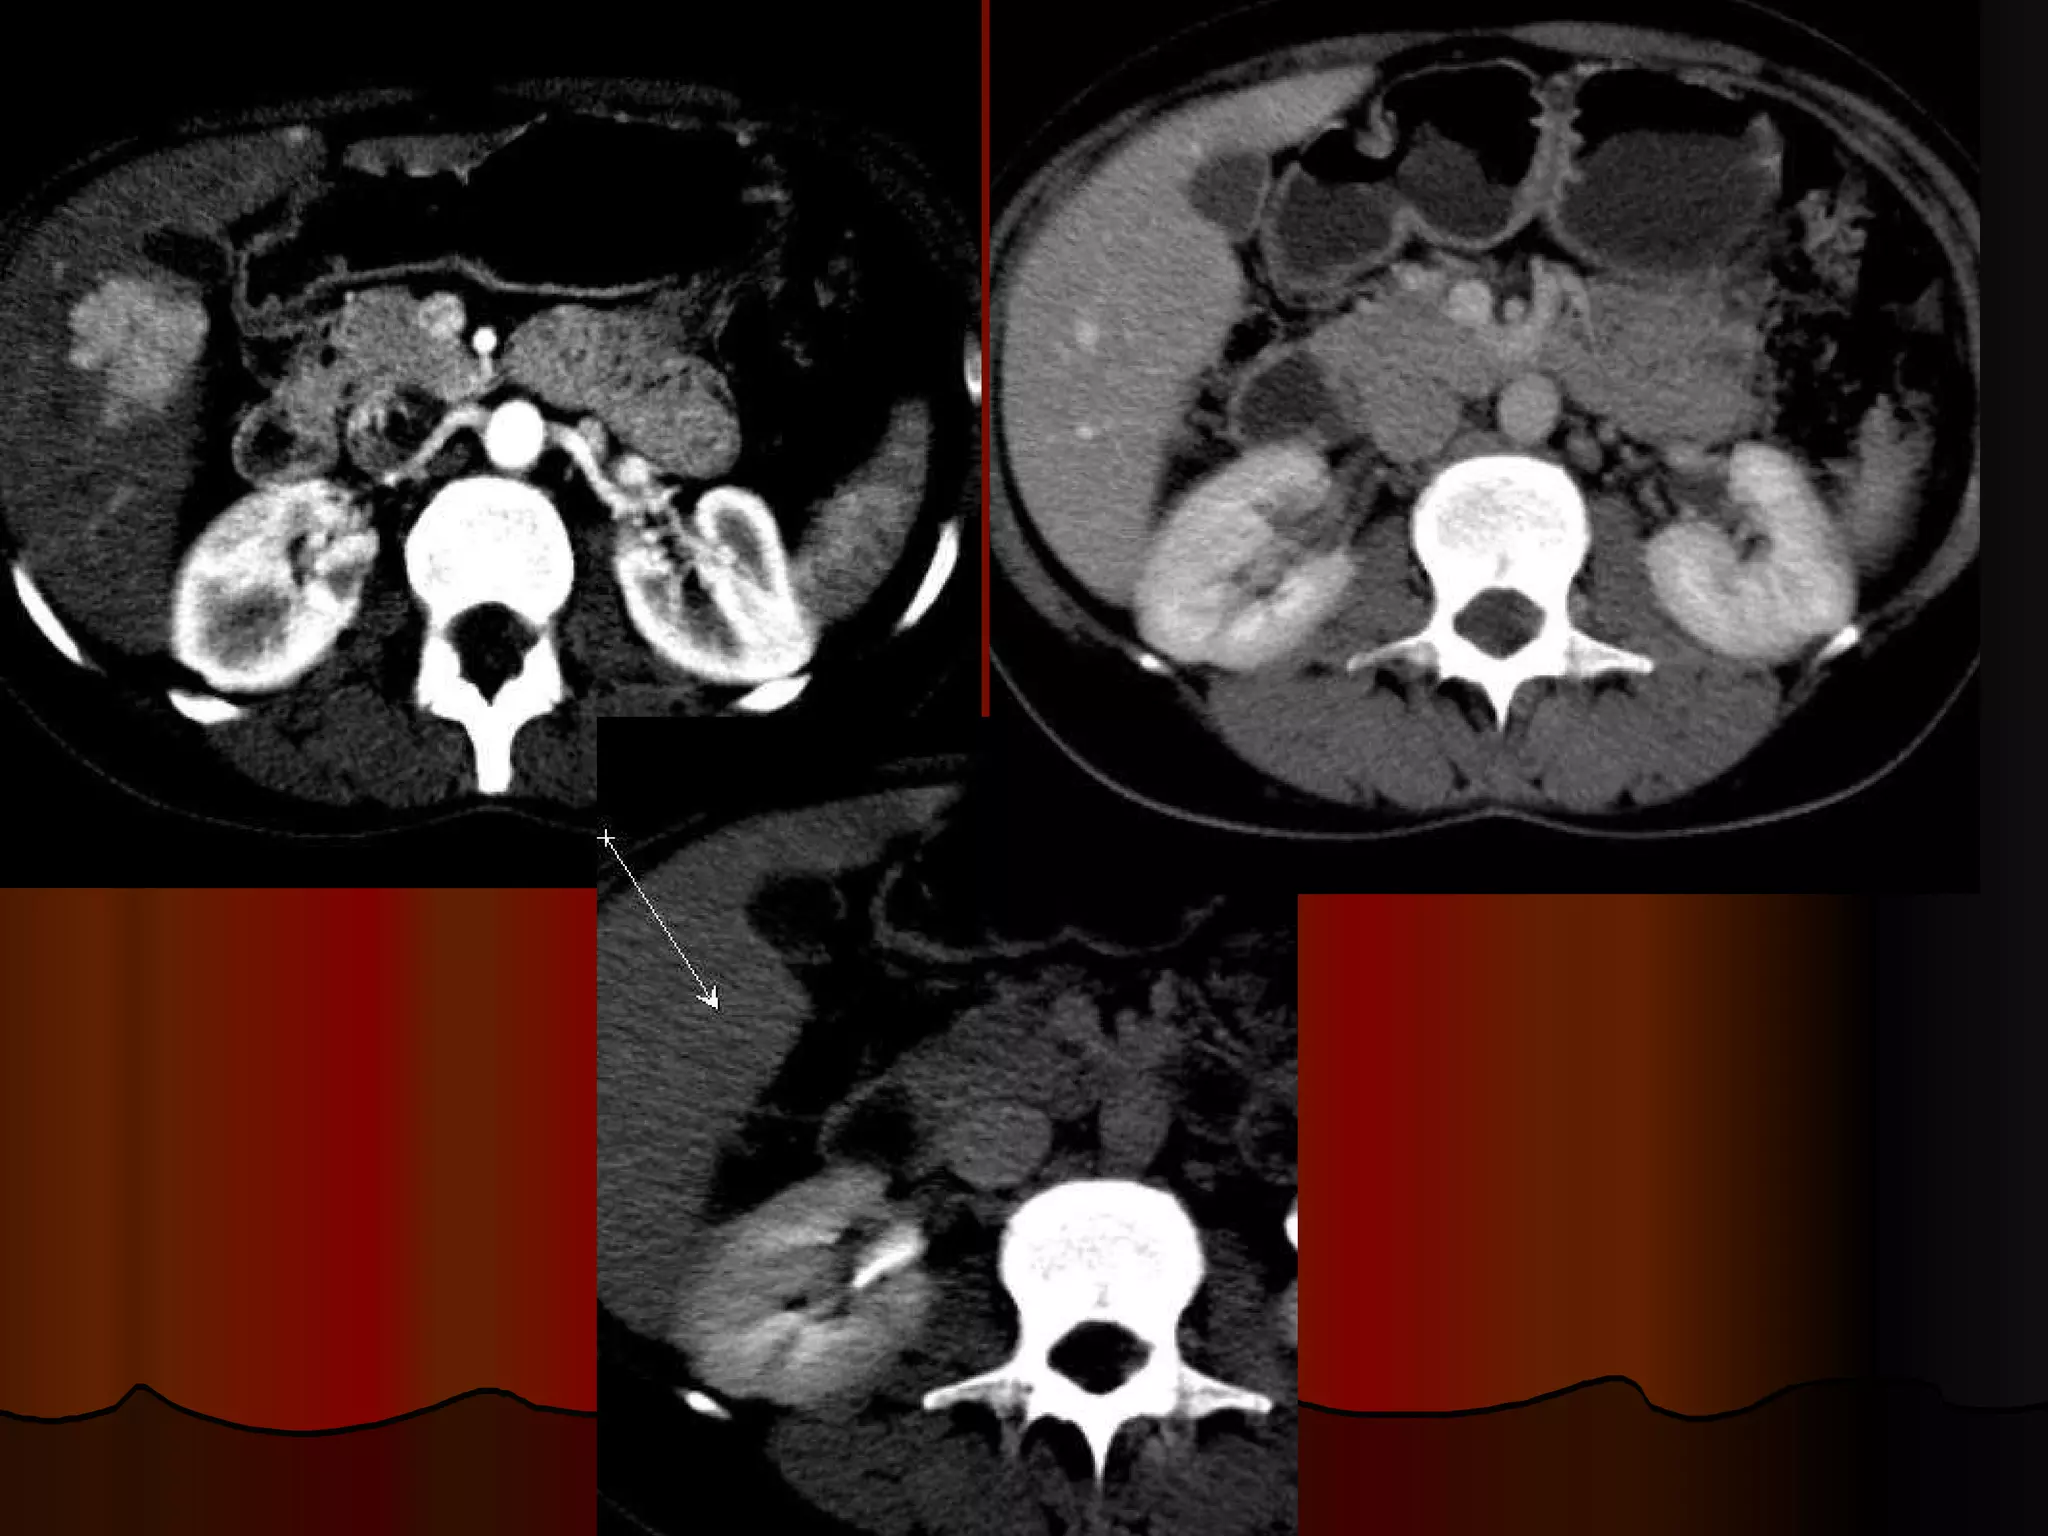

Случай 1. - женщина, 60 лет, госпитализирована в отделение сосудистой хирургии с диагнозом острый тромбоз левой бедренной артерии при скриннинговом УЗИ брюшной полости над мочевым пузырем обнаружено опухолевидное образование  из анамнеза – жалобы на боли в левой ноге, абдоминальных болей, нарушений частоты или консистенции стула не предъявляет при пальпации  объемное эластичное подвижное образование в гипогастральной зоне, чувствительное при глубокой пальпации. В анализах – умеренная гипохромная анемия. Гинекологический статус – без патологических находок. Ирригография– без патологических находок.

КТ-находки Образование с признаками экспансивного роста Локализация -  интраперитонеально инфрамезентериально по срединной линии  По строению напоминает кишечную трубку с циркулярным утолщением стенок, прослеживается их слоистость, просвет выполнен воздухом и жидкостью, четкие контуры Органная принадлежность – подвздошная кишка/ брыжейка, однако не видно типично «входящей» и «отходящей» петли, скорее прилежит к протитво-брыжеечному краю Гомогенно усиливается без признаков гиперваскулярности, внутренний «слой» гиподенсный Нет признаков кишечной обструкции, реакции перифокального жира, лимфаденопатии, подвздошые сосуды не компрессированы, печень не поражена Пристеночный линейный тромб на уровне устья  общей подвздошной артерии слева

Вопросы для дискуссии Сообщение с просветом кишки - следствие некроза или естественный просвет? Почему нет признаков кишечной обструкции? Если опухоль, то какая? Возможно ли, что не опухоль, учитывая анатомическую область?

Случай 1. -женщина, 60 лет, госпитализирована в отделение сосудистой хирургии с диагнозом острый тромбоз левой бедренной артерии при скриннинговом УЗИ брюшной полости над мочевым пузырем обнаружено опухолевидное образование из анамнеза – жалобы на боли в левой ноге, абдоминальных болей, нарушений частоты или консистенции стула не предъявляет при пальпации объемное эластичное подвижное образование в гипогастральной зоне, чувствительное при глубокой пальпации. В анализах – умеренная гипохромная анемия. Гинекологический статус – без патологических находок. Ирригография– без патологических находок.

КТ-находки Образование спризнаками экспансивного роста Локализация - интраперитонеально инфрамезентериально по срединной линии По строению напоминает кишечную трубку с циркулярным утолщением стенок, прослеживается их слоистость, просвет выполнен воздухом и жидкостью, четкие контуры Органная принадлежность – подвздошная кишка/ брыжейка, однако не видно типично «входящей» и «отходящей» петли, скорее прилежит к протитво-брыжеечному краю Гомогенно усиливается без признаков гиперваскулярности, внутренний «слой» гиподенсный Нет признаков кишечной обструкции, реакции перифокального жира, лимфаденопатии, подвздошые сосуды не компрессированы, печень не поражена Пристеночный линейный тромб на уровне устья общей подвздошной артерии слева

Вопросы для дискуссииСообщение с просветом кишки - следствие некроза или естественный просвет? Почему нет признаков кишечной обструкции? Если опухоль, то какая? Возможно ли, что не опухоль, учитывая анатомическую область?